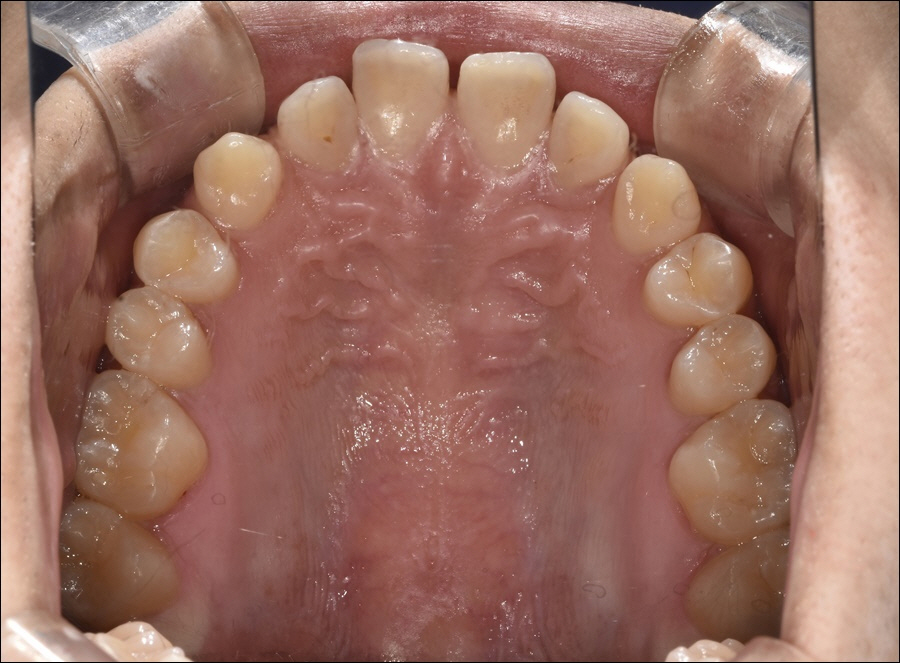

치아 배열이 고르지 못할 경우,

심미적으로 만족도가 떨어질 뿐만

아니라 다양한 기능적 불편함을

느낄 수 있기 때문에 치과 내원을

통해 본인의 구강 상태를 정확하게

진단하여 올바른 치료를 제 때

관리받아야 했어요.

울퉁불퉁하거나 치아끼리 서로 겹쳐

있는 상태는 아무리 노력해도 청결한

상태를 유지하기 힘들다고 했어요.

음식물이 치아 사이에 끼었을 때,

깨끗하게 제거하는 과정에도 많은

어려움을 호소하기 때문에 적극적인

문제 해결을 위한 교정 치료를 통해

다양한 문제를 개선할 수 있었습니다.

신논현역 옥스치과의 대표원장님께서는

덧니, 반대교합, 과개교합, 돌출입 등의

다양한 부정 교합 고민을 안고 있는

환자분들에게 수준 높은 교정 노하우를

선보이고 있었어요.

오차 없는 진단을 위하여 3D 디지털

스캔 방식으로 환자마다 모두 다른

치아 상태를 검사하여, 이를 토대로

치료 계획을 수립하고 있었으며,

성공적인 치료 결과를 오래 유지할 수

있도록 철저한 사후관리 시스템까지

진행하여 환자분들의 믿음에

보답하고 있었습니다.